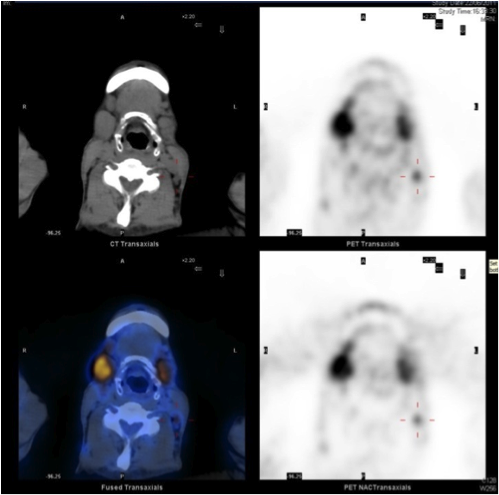

Three months later, patient was admitted for obstructive jaundice. His liver function was deranged with bilirubin 132, ALP 386, ALT 346. Ultrasound abdomen showed dilated common bile duct. Patient had the endoscopic retrograde cholangiopancreatography (ERCP) done and it found smooth stricture at common hepatic duct close to hila. Ampulla biopsy showed benign small bowel mucosa with focal neutrophilic intraepithelial infiltration and ulceration. There was no evidence of malignancy. Contrast CT abdomen and pelvis was also performed. It revealed again dilated common bile duct. Also there were multiple enlarged portal, mesenteric, retroperitoneal and groin lymph nodes. He had a 1cm cystic lesion at the tail of pancreas. In view of suspected malignancy, positron emission tomography (PET) was done (Fig 3A, 3B). There was no hypermetabolic lesion in liver and pancreas, but multiple hypermetebolic lymph nodes were found in head, neck, thorax, abdomen and pelvis. Also the bilateral submandibular glands showed intense FDG uptake with SUV max 7.5.

Excisional biopsy of submandibular gland with a diagnostic testing was performed. It showed lymphoid infiltrate with marked atrophy and perilobular and septal sclerotic fibrosis. The lymphoid infiltrate mainly consisted of small lymphocytes and large number of plasma cells. Immunohistochemical studies found most of the plasma cells positive for IgG and IgG4. So, the pathology suggested chronic sclerosing sialadenitis, consistent with IgG4-related disease. The ampulla specimen obtained in previous ERCP was also positive in IgG4 staining. The serum IgG4 level was checked and elevated to 102.9 g/L (normal range <2).